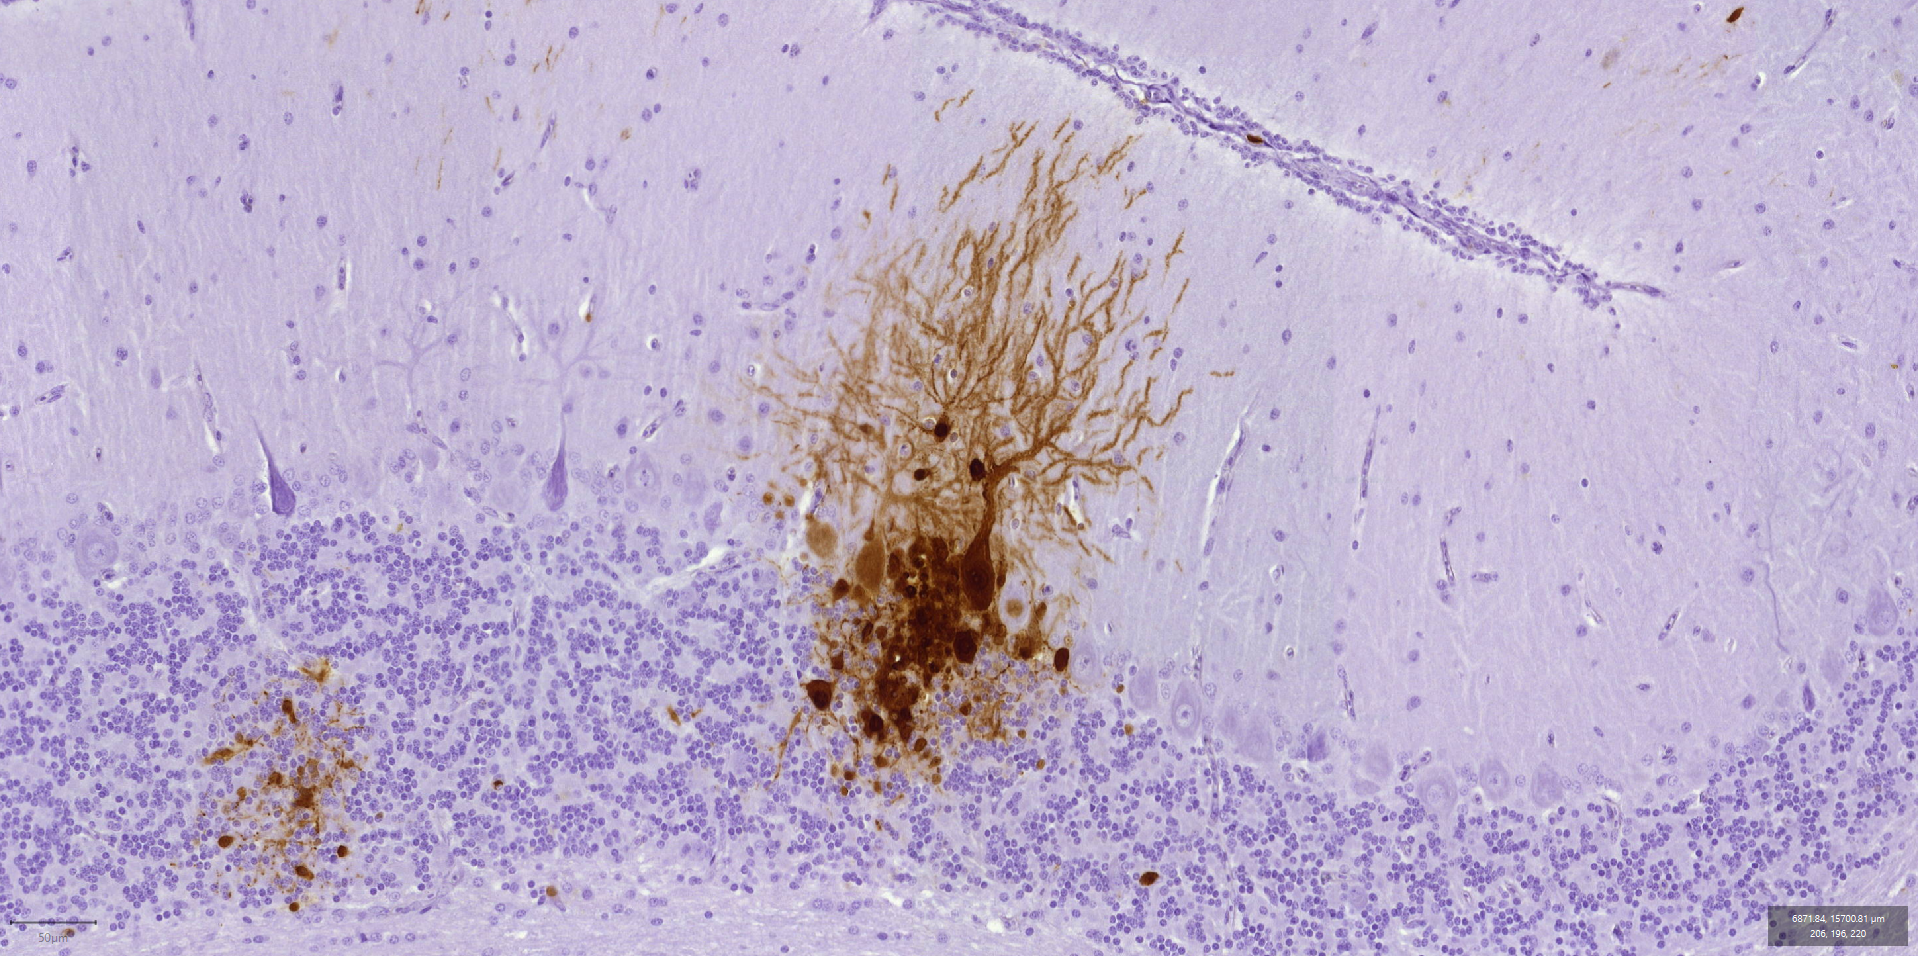

Images de cerveau de poulet et de canard observé au microscope, avec le virus marqué en marron.